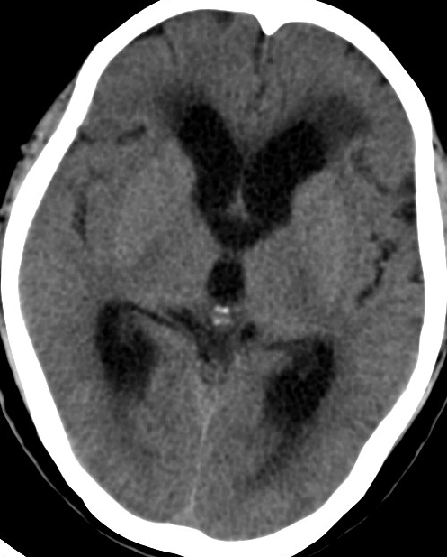

2013-8-2 CT

腰穿脑压240